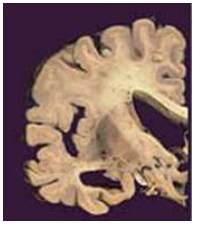

A Demência é um grave prejuízo na memória, julgamento, orientação e cognição. A figura abaixo apresenta que tipo de demência:

Assinale a alternativa CORRETA: